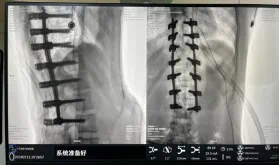

據悉脊柱側彎手術治療后可以保持軀干平衡,改善外觀并防止畸形進一步發展。患者的生活質量得到提高,進而減少脊柱過度畸形可能帶來的疾病的發生率,外觀上的積極變化往往也能帶來患者心理與精神的積極變化。臨床上會綜合考慮患者的年齡、側彎程度、進展趨勢、骨質條件、鄰近節段情況、手術節段等因素,合理采用個性化的手術方式進行治療。然而,由于脊柱神經血管密布,手術操作相對復雜,手術難度高、風險大,傳統脊柱側彎的手術方式往往有較高的神經或脊髓損傷風險。故此次科室決定開展機器人輔助導航下脊柱側彎矯形、植骨融合內固定手術。術前,醫生團隊在機器人多維度圖像融合智能手術規劃功能的輔助下,預先規劃了理想的置釘路徑。術中,天璣骨科手術機器人準確遵循術前規劃,根據配準結果,實時定位并準確執行置釘操作,所有導針均用電鉆置入,一次性成功,協助醫生順利完成手術。最終,在麻醉科、手術室密切配合下,歷時3小時成功完成側彎矯形術,出血量僅500ml。術后,患者恢復良好,大小便及下肢神經運動感覺正常。

1721799619109861.jpg

圖為置釘后

此次在充分保證患者安全和手術效果的前提下使用機器人輔助下手術的成功實施,大大降低了高難度手術的風險,并進一步減輕了患者手術創傷、縮短了康復時間。這也標志著南方醫院贛州醫院脊柱外科治療個性化、精準化、智能化水平進一步提升。